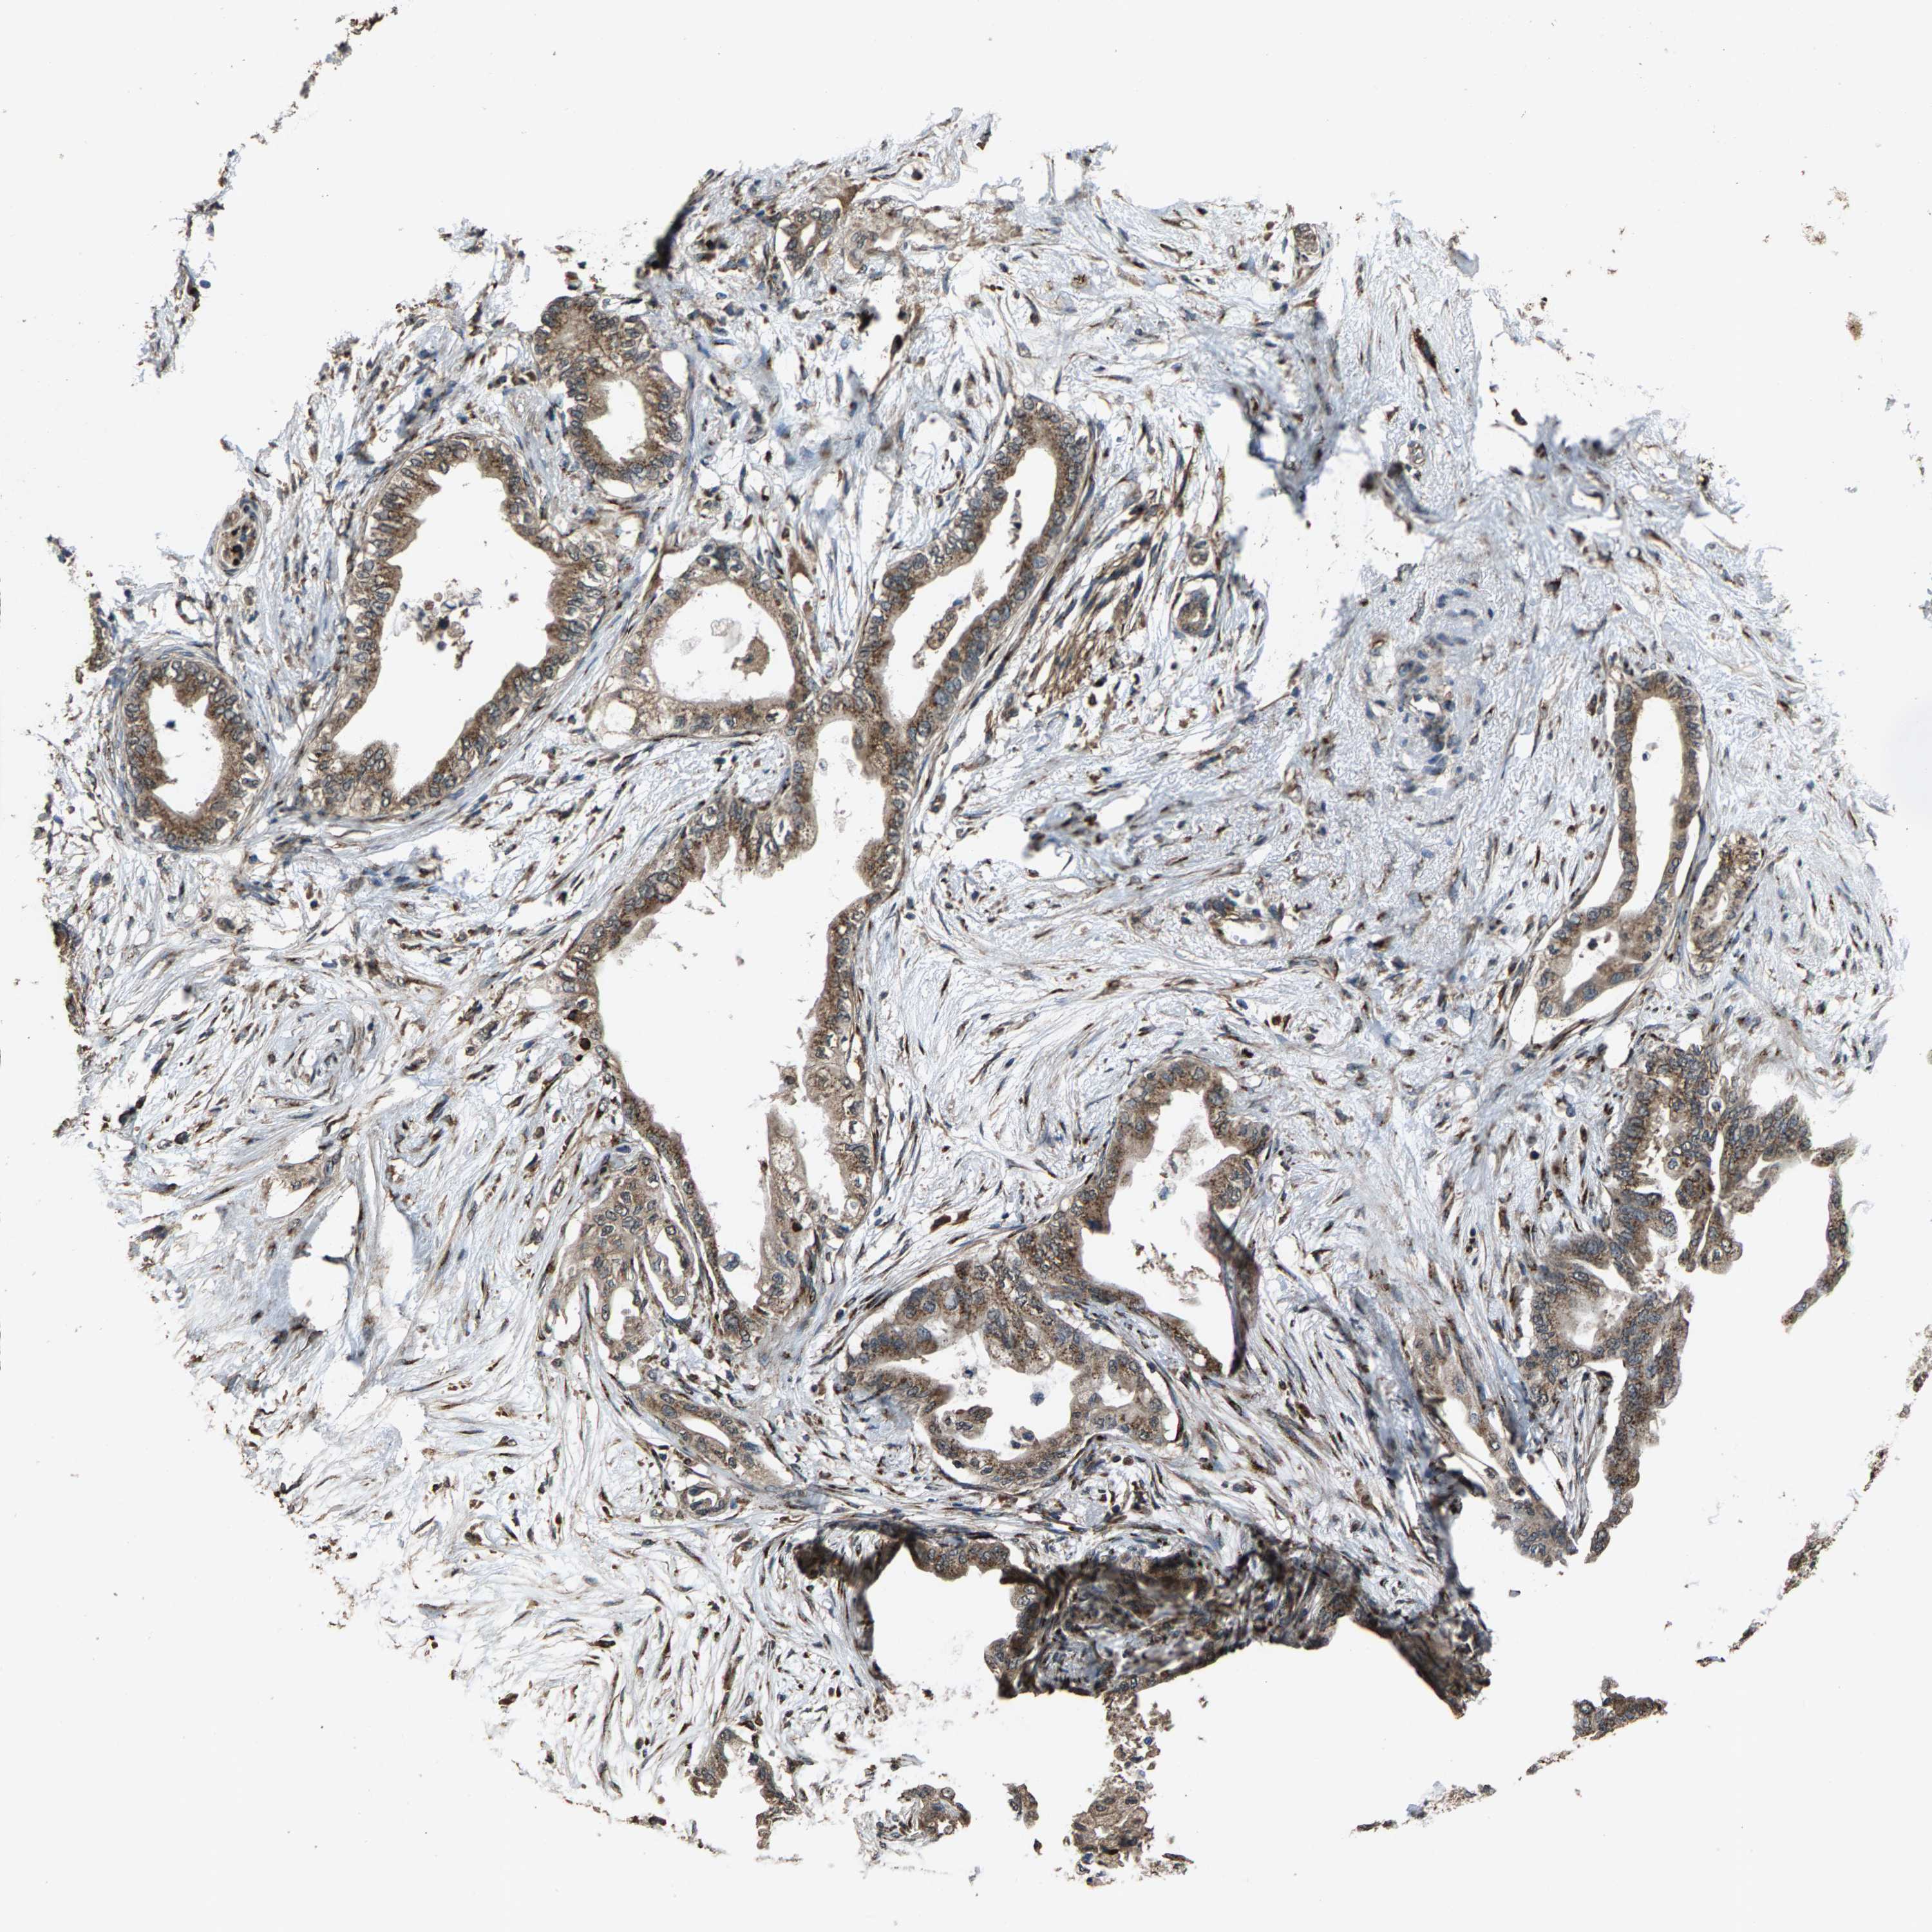

PANCREATIC CANCER - Protein expressioni

A mouse-over function shows sample information and annotation data. Click on an image to view it in a full screen mode. Samples can be filtered based on level of antibody staining by selecting one or several of the following categories: high, medium, low and not detected. The assay and annotation is described here.

Note that samples used for immunohistochemistry by the Human Protein Atlas do not correspond to samples in the TCGA dataset.

Antibody stainingi

Antibody staining in the annotated cell types in the current human tissue is reported as not detected, low, medium, or high, based on conventional immunohistochemistry profiling in selected tissues. This score is based on the combination of the staining intensity and fraction of stained cells.

Each image is clickable and will lead to virtual microscopy that enables deeper exploration of all samples and also displays staining intensity scores, fraction scores and subcellular localization as well as patient and tissue information for each sample.

Antibody HPA021374

Antibody HPA023161

Antibody HPA024631

Staining

High

Medium

Low

Not detected

Intensity

Strong

Moderate

Weak

Negative

Quantity

>75%

75%-25%

<25%

None

Location

Nuclear

Cytoplasmic/membranous

Cytoplasmic/membranous,nuclear

Adenocarcinoma, NOS